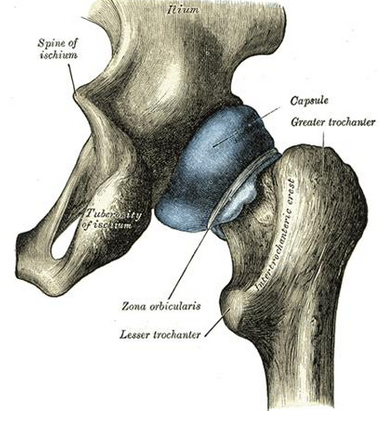

Describe course of obturator internus

origin

Path

Insertion

Origin: ischiopubic ramus & obturator membrane

Path:

THrough lesser sciatic notch

makes a 90 degree turn

Insertion: Medial aspect of GT